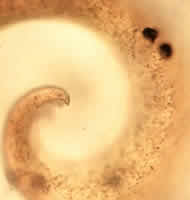

A 38-year-old HIV-positive man was seen at a local AIDS clinic for chronic

cough and hemoptysis (blood in sputum). A bronchoalveolar lavage

(BAL) was performed and an object believed to be nematode larva was observed

in one of the stained smears of the BAL. A single object was seen

and is shown below at 100×, 400×, and 1000× magnification. The object

measured approximately 440 micrometers in length by 30 micrometers in

maximum diameter. What is your diagnosis? Based on what criteria?